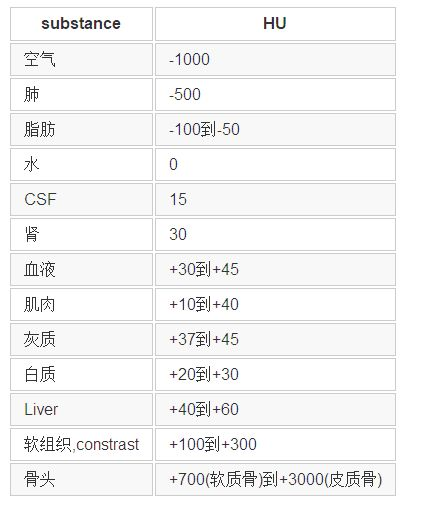

这部分内容比较杂乱。因为不同的任务、不同的数据集,通常数据预处理的方法有很大不同。但基本思路是要让处理后的数据更有利于网络训练。那么二维图像预处理的一些方法都是可以借鉴的,如对比度增强、去噪、裁剪等等。此外还有医学图像本身的一些先验知识也可以利用,比如CT图像中不同仿射剂量(单位:HU) 会对应人体不同的组织器官。

不同放射剂量对应的组织器官

基于上表,可以对原始数据进行归一化处理:

image = image-meam上述归一化处理适用于绝大多数数据集,其他一些都是可有可无的针对于具体数据的操作,这些操作包括上面的MIN_BOUND 和MAX_BOUND 都最好参考优秀论文的开源代码的处理方式。